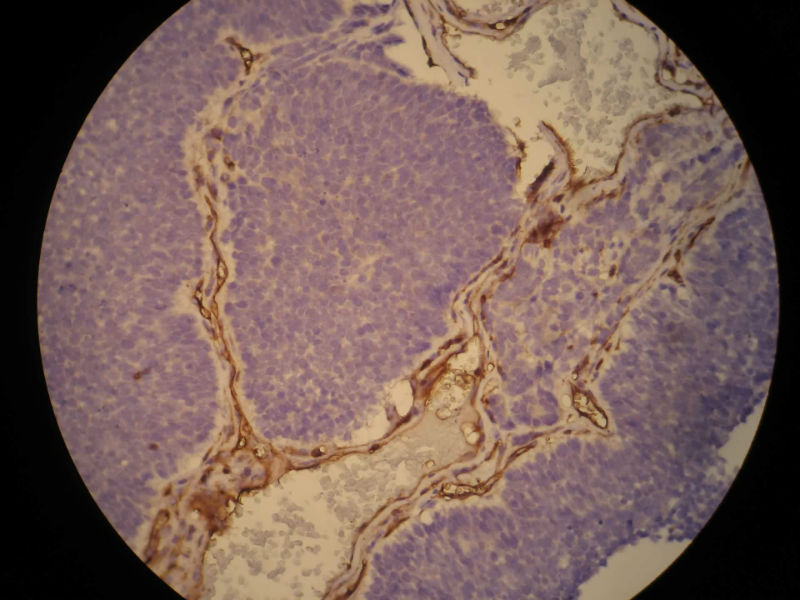

患者,M50Y,左侧肢体乏力半个月,肌力2级

MRI示右顶叶和小脑占位性病变,增强强化明显

术中见鱼肉样质脆,血管丰富,边界不清,部分囊性变,分块切除

大体:碎组织,4.2*3.5*2cm,呈鱼肉状,质嫩软。其间可见少量灰白组织,质韧。

Based on histology and immunohistochemistry, metastatic neuroendocrine carcinoma needs to be ruled out. I suggest TTF-1 stain. Also pay attention to nuclear morphology at high power view and see if it fits small cell carcinoma. It doesn't have to be a primary CNS tumor just because the border appears infiltrative.

谢谢Dr.mjma和楼上各位的指导。形态学符合小细胞癌。我们加做TTF-1,CD56和NSE,下周有结果。